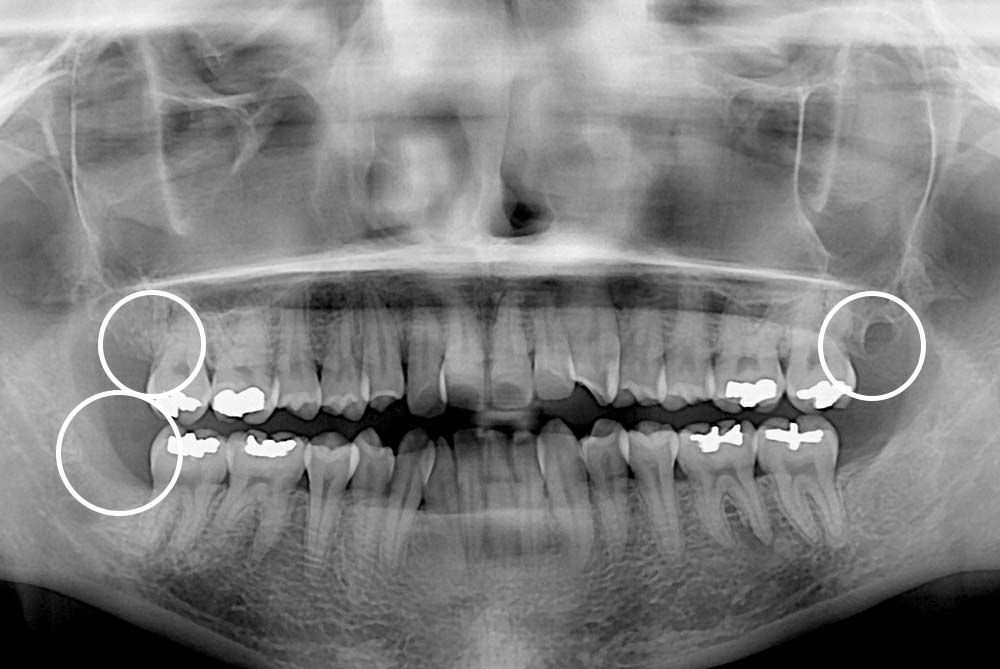

[사랑니] 매복 사랑니 발치

치료후 : 2019-10-29

세종치과는 구강악안면외과학 박사이신 원장님이 발치하는 치과입니다.